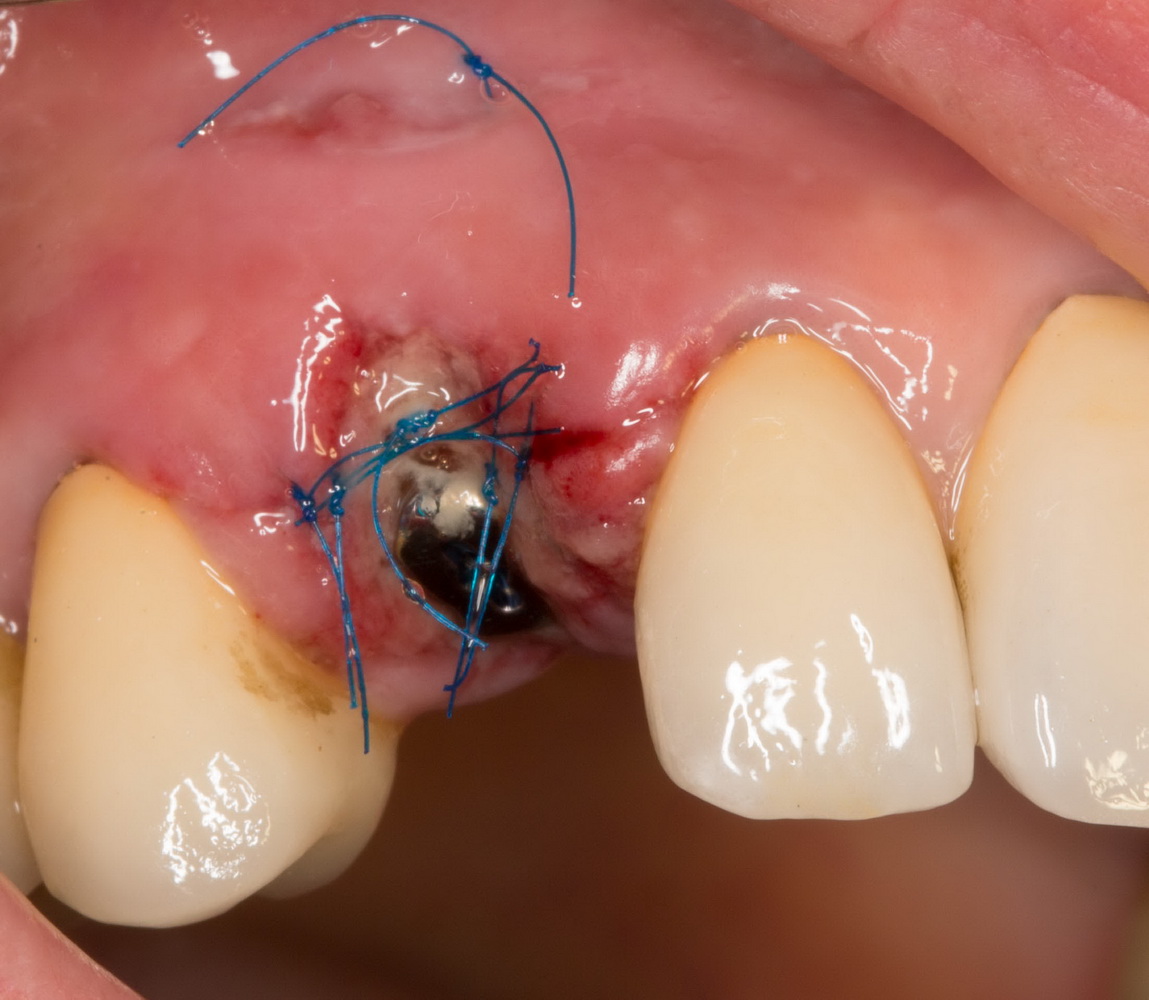

Итак, накладывается Mucograft Seal. Также успешно можно использовать любую коллагеновую матрицу любого размера:

Он подшивается узловыми швами. Операция закончена. Вид послеоперационной раны:

или вот: